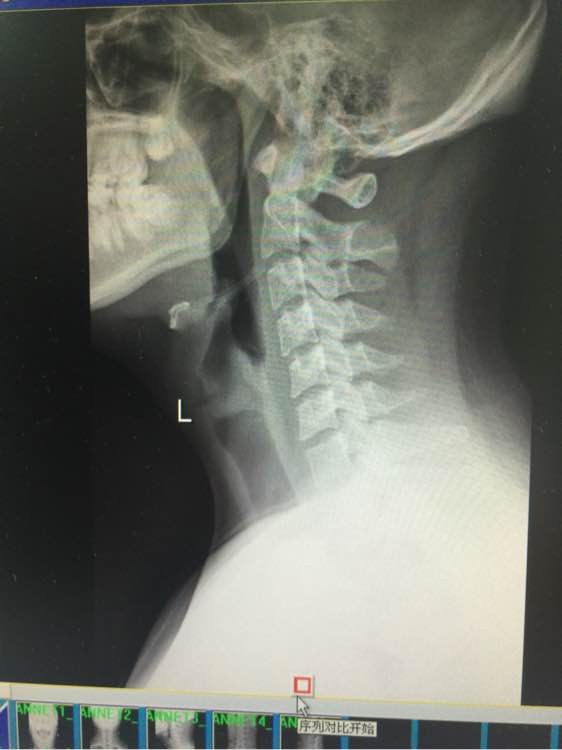

求吧友们帮我看看,寰枢椎关节半脱位,供血不足

寰枢椎半脱位引发的眩晕,手法复位1-2次即可

寰枢椎半脱位可以通过牵拉旋转头部使之归位。不难治啊。跟脱臼治法差不多。对了你颈椎上带的东西对你这病作用不大。赶紧找个正骨的复位。。。。。。

确认一下脊髓有没受伤,看图你不严重可以自己修复,就是扶正骨头。

脊髓略受压,没受伤

椎体对血管有压迫。脖子上的那玩意最好不带,时间长了会让寰枢关节变松,脑袋变成拨浪鼓。

被医生吓坏了,不过是第一颈椎左旋了一点,导致一边的入脑的肺动脉憋住,所以大脑缺氧头晕,寰椎和头颅接缝是不动椎,如果脱位你早就瘫了。平躺,头抬起来,迅速常鼻子方向15度旋转复位,听到卡擦就放手,复位后就脑供血正常了。